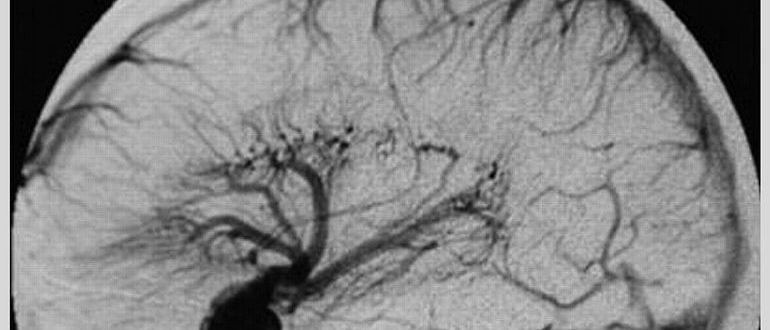

Мр картина венозной ангиомы левой гемисферы мозжечка - 96 фото